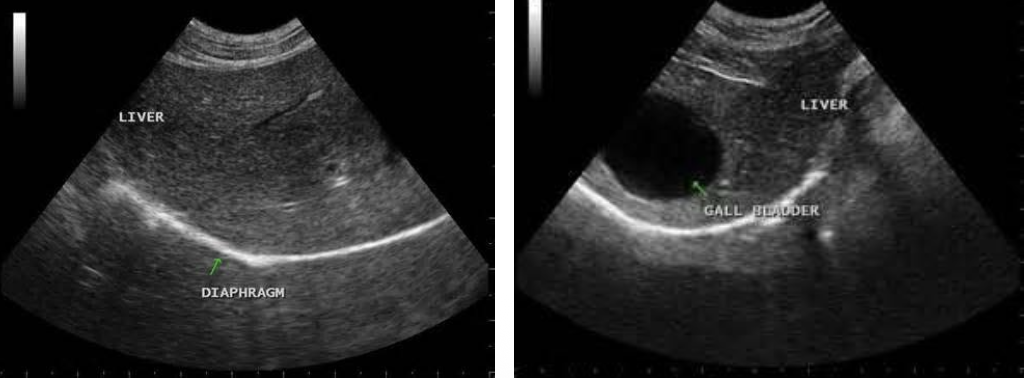

Liver

coarsely grained

large vessels, gallbladder is visible

diaphragm lies beneath the liver